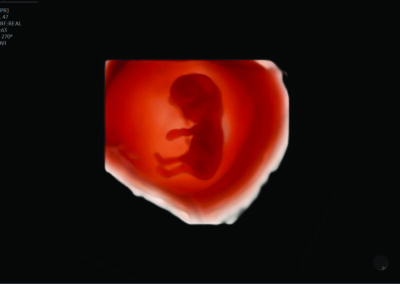

Comprehensive, advanced and expert MFM care for high-risk pregnancies

- Multiple births